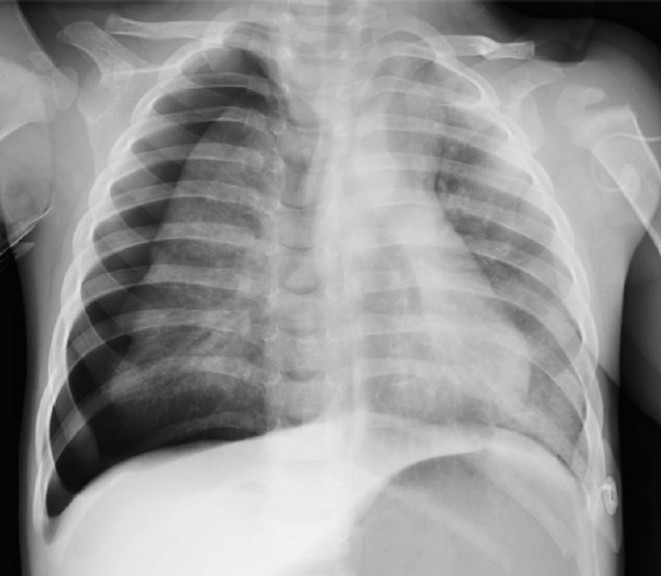

Paediatric blunt chest trauma

You are the resuscitation consultant in a paediatric major trauma centre. A 12-year-old girl is brought in by her parents …